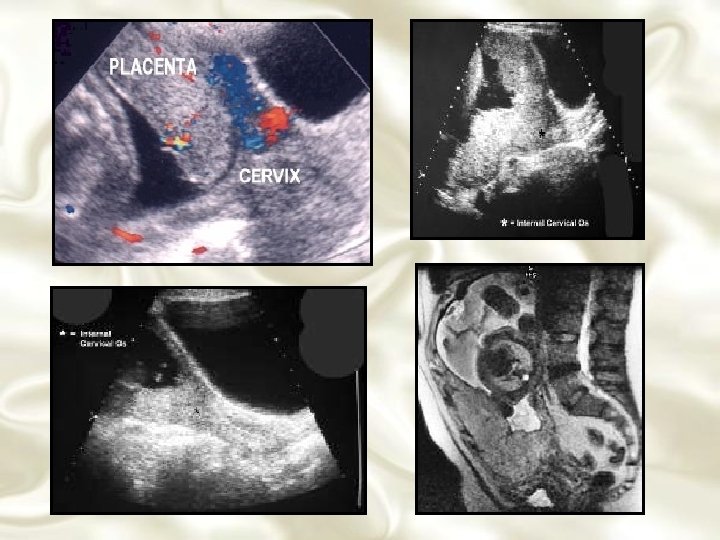

DIAGNÓSTICO LABORATORIAL • Exame hematológico • Pesquisa de hemáceas fetais • Localização da placenta – Métodos radiológicos – Rx, angiografia, arteriografia, amniografia, cistografia, proctografia • Migração placentária

Placenta Prévia Identificação ultra-sonográfica de placenta prévia e doença clínica subsequente